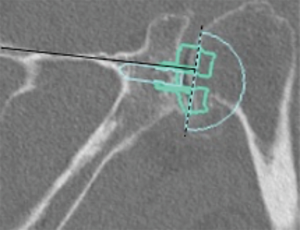

Prosthetic malalignment (Figure 2) can cause dislocation of RSA if excessive anterior version of the glenosphere and/or excessive retroversion of the humeral component, resulting in abutment of the humerosocket against the glenoid neck during internal rotation (3,6,12,15,25,34). However, it is still unclear how much misalignment of the component can be considered a risk to RSA stability.

In a level III study, Tashjian et al. analyzed 168 RSAs with 13% of instability found the only risk factor significantly associated with instability was the superior inclination of the baseplate after controlling for age, sex, body mass index, and primary versus revision procedure (24). This fact emphasizes the importance of preoperative planning and meticulous placement of the baseplate. Inclination of the glenoid can be reliably measured on true anteroposterior radiographs of the shoulder joint using the beta-angle described by Maurer et al. (39). Given that the correct position of the baseplate occupies the inferior two thirds of the glenoid, recently Daggett et al. proposed a modification to this measurement called the “reverse shoulder angle” to avoid underestimation of glenoid inclination (40) (Figure 3). Although 15º of inferior tilt of the baseplate was demonstrated to be associated with decreased rates of glenoid loosening and failure (2,16), further studies are necessary to correlate baseplate inclination with instability risk.

Detailed imaging of the shoulder including true anterior-posterior in the scapular plane (Grashey), axillary and scapular Y view X-rays must be complemented by computed tomography (CT). CT scan allows the best accuracy to assess glenoid morphology (42,49). Precise measurements of version, inclination, and depth of the glenoid are important to central peg and fixation screw placement in areas with the best remaining native bone stock. The goal is to implant the baseplate as low as possible, placing the central peg parallel within 10º to 15º of inferior tilt in relation to the line of the supraspinatus fossa (34). Three-dimensional preoperative planning software and patient-specific instrumentation are useful tools that have been validated (42), but outcome and cost-effectiveness data are not yet available.

Glenoid inclination in the vertical plane is another important measurement when planning glenoid baseplate positioning. Inferior tilt greater than 15º was shown to correlate with early glenoid loosening and failure (2,16). Tashjian et al. reported increased rates of instability after RSA with increased beta-angle (24). Although glenoid inclination can be reliably measured using the beta angle (39,42), it can be underestimated when planning a RSA. Recently Daggett et al. proposed the “reverse shoulder angle” which seems to be more specific for RSA baseplate fixation (40) (Figure 3B).